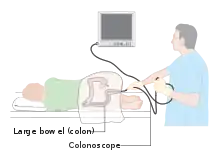

Colonoscopy (/ˌkɒləˈnɒskəpi/) or coloscopy (/kəˈlɒskəpi/)[1] is a medical procedure involving the endoscopic examination of the large bowel (colon) and the distal portion of the small bowel. This examination is performed using either a CCD camera or a fiber optic camera, which is mounted on a flexible tube and passed through the anus.[2][3]

The purpose of a colonoscopy is to provide a visual diagnosis via inspection of the internal lining of the colon wall, which may include identifying issues such as ulceration or precancerous polyps, and to enable the opportunity for biopsy or the removal of suspected colorectal cancer lesions.[4][5]

The first step is usually a digital rectal examination (DRE), to examine the tone of the anal sphincter and to determine if preparation has been adequate. A DRE is also useful in detecting anal neoplasms and the clinician may note issues with the prostate gland in men undergoing this procedure.[55] The endoscope is then passed through the anus up the rectum, the colon (sigmoid, descending, transverse and ascending colon, the cecum), and ultimately the terminal ileum. The endoscope has a movable tip and multiple channels for instrumentation, air, suction and light. The bowel is occasionally insufflated with air to maximize visibility (a procedure that gives the patient the false sensation of needing to take a bowel movement). Biopsies are frequently taken for histology. Additionally in a procedure known as chromoendoscopy, a contrast-dye (such as indigo carmine) may be sprayed through the endoscope onto the bowel wall to help visualize any abnormalities in the mucosal morphology. A Cochrane review updated in 2016 found strong evidence that chromoscopy enhances the detection of cancerous tumors in the colon and rectum.[56]